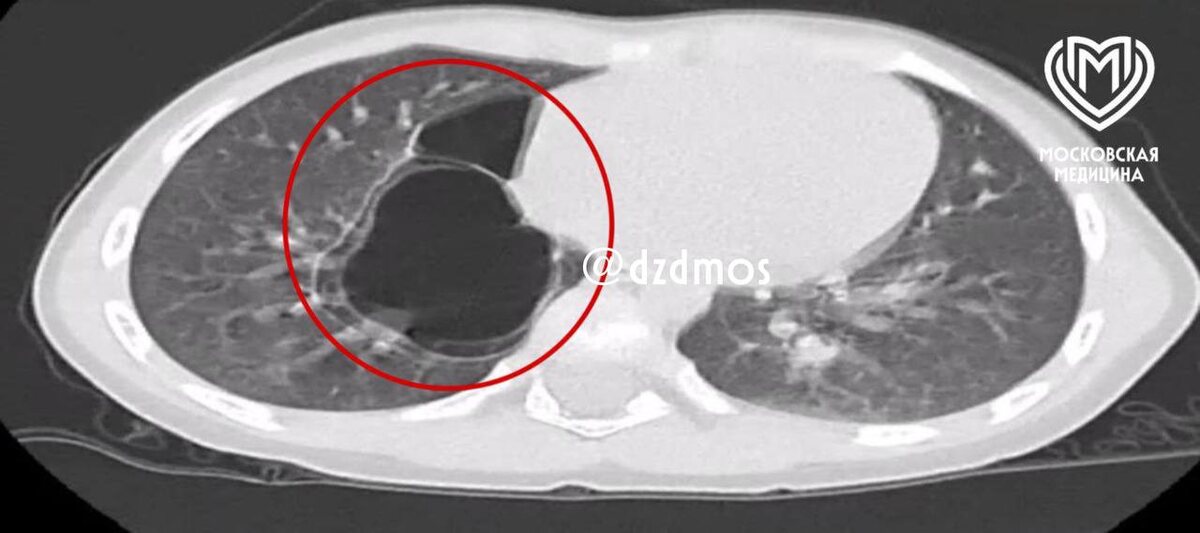

Из лёгких ребенка столичные врачи удалили кисту размером с апельсин

«По словам мамы, малышка часто болела ОРВИ и бронхитами. На рентгенографии медики визуализировали уплотнения в правом лёгком, и для уточнения диагноза провели компьютерную томографию, которая показала врождённый порок развития — кистозно-аденоматозную мальформацию лёгких», — рассказали в больнице.

При этой патологии нормальная лёгочная ткань замещается аномальной и происходит образование кист. С возрастом они могут расти и привести к дыхательной недостаточности, осложненным пневмониям, слабой вентиляции лёгких.

«Во время операции маленькой пациентке сделали торакоскопию. То есть через небольшой разрез в грудной клетке вошли в плевральную полость и с помощью специального мешка извлекли два разнокалиберных тонкостенных кистовидных образования, размером до 6 см и до 3 см, в которых находилось ещё мелкие кисты», — объяснил Ампар Фатима, детский хирург хирургического отделения №2.